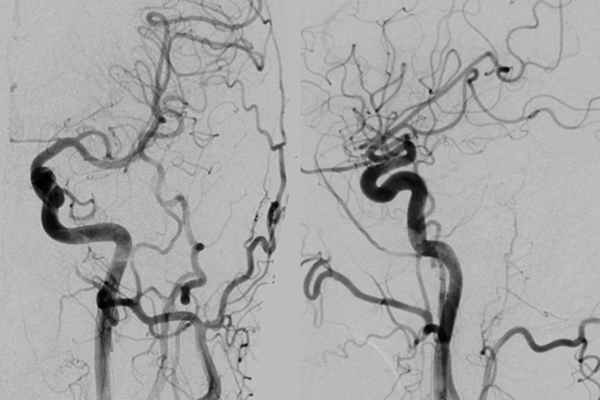

▲左颈动脉正侧位造影显示左侧大脑前动脉A1段发育纤细

▲右侧颈动脉正侧位造影显示交通段小凸起

三维DSA证实为后交通动脉起始部圆锥

排除出血责任病灶

右侧A1优势,前交通动脉开放